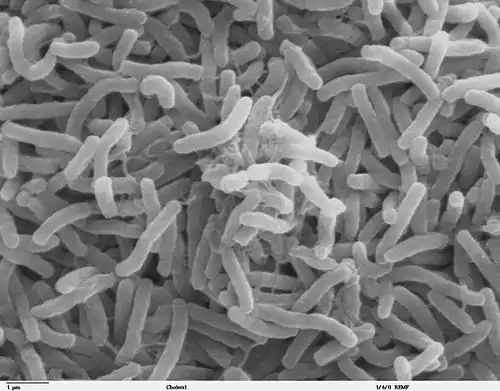

Cholera